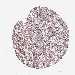

LIVER CANCER - Protein expressioni

A mouse-over function shows sample information and annotation data. Click on an image to view it in a full screen mode. Samples can be filtered based on level of antibody staining by selecting one or several of the following categories: high, medium, low and not detected. The assay and annotation is described here.

Antibody stainingi

Antibody staining in the annotated cell types in the current human tissue is reported as not detected, low, medium, or high, based on conventional immunohistochemistry profiling in selected tissues. This score is based on the combination of the staining intensity and fraction of stained cells.

Each image is clickable and will lead to virtual microscopy that enables deeper exploration of all samples and also displays staining intensity scores, fraction scores and subcellular localization as well as patient and tissue information for each sample.

Antibody HPA042411

Staining

High

Medium

Low

Not detected

Intensity

Strong

Moderate

Weak

Negative

Quantity

>75%

75%-25%

<25%

None

Location

Nuclear

Cytoplasmic/membranous

Cytoplasmic/membranous,nuclear

Cholangiocarcinoma

Carcinoma, Hepatocellular, NOS